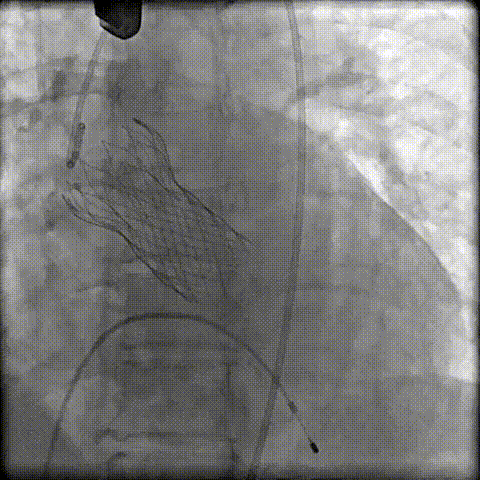

术前冠脉评估

“右足”+“左头”根部造影评估